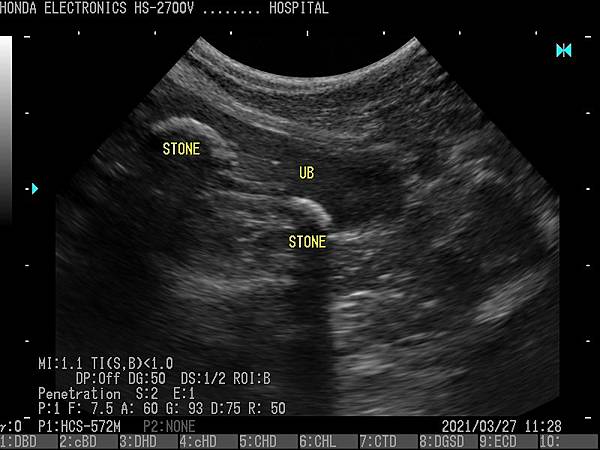

- 通過H-res獲得清晰豐富的單色圖像

HONDA獨創的圖像增強技術 H-res(我們的分辨率技術)

多年來超聲波技術的發展,結晶為“ H-res”圖像增強技術。

可以通過針對每種應用和探頭調整“ H-res”參數來獲得最佳圖像。

* 分辨率可在較淺的區域可視化精細的組織結構。* 穿透力可以在更深的器官中顯現出良好的分辨率。* 邊界可視化骨骼以進行觀察。* 清晰度降低了血管中的噪音。* 溫和會降低圖像增強效果。* OFF具有直接的超聲圖像。